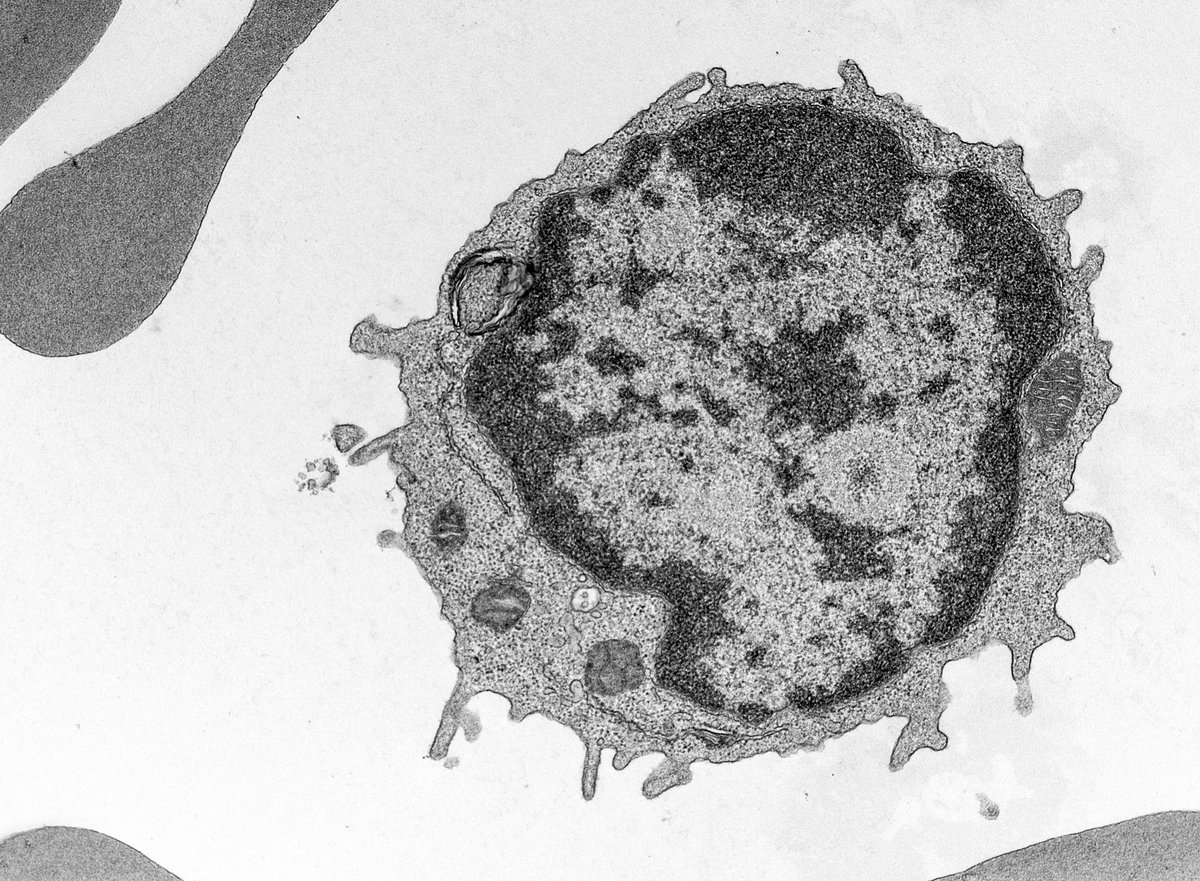

White blood cell, a lymphocyte, at 5000x from a blood sample ~5 micrometers across. Lymphocytes are immune cells that can recognize and respond to antigens, produce antibodies, kill virus infected/tumor cells and regulate other immune cells. #biology #ImmuneSystem